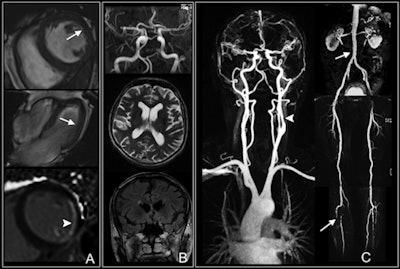

In the current study, the researchers enrolled 65 patients with type 1 or type 2 diabetes and a disease duration of at least 10 years. The patients underwent contrast-enhanced whole-body MRI exams, including brain, cardiac, and vascular sequences at baseline, between June 2005 and December 2006. Imaging was performed on either a 3- or 1.5-tesla system (Magnetom Tim Trio or Magnetom Avanto, Siemens Healthcare).

The prevalence of any findings at whole-body MRI was considered high (66%) by the authors. In addition, the prevalence of findings was similar between cardiovascular (36%), cerebrovascular (39%), and peripheral vessel imaging (43%).

Breaking down the results further, positive late gadolinium enhancement in any myocardial segment had the highest prevalence (28%) among cardiac findings, while an abnormal amount of white-matter lesions had the highest prevalence among cerebrovascular findings (23%).